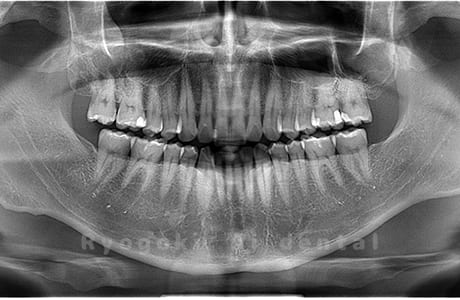

Case10

- 原因

- 下顎左の親知らず

- 治療内容

- 下顎左の親知らずを抜歯したケースです。

<リスク・副作用>

手術後は痛み、腫れ、痺れなどの副作用が生じる場合があります。